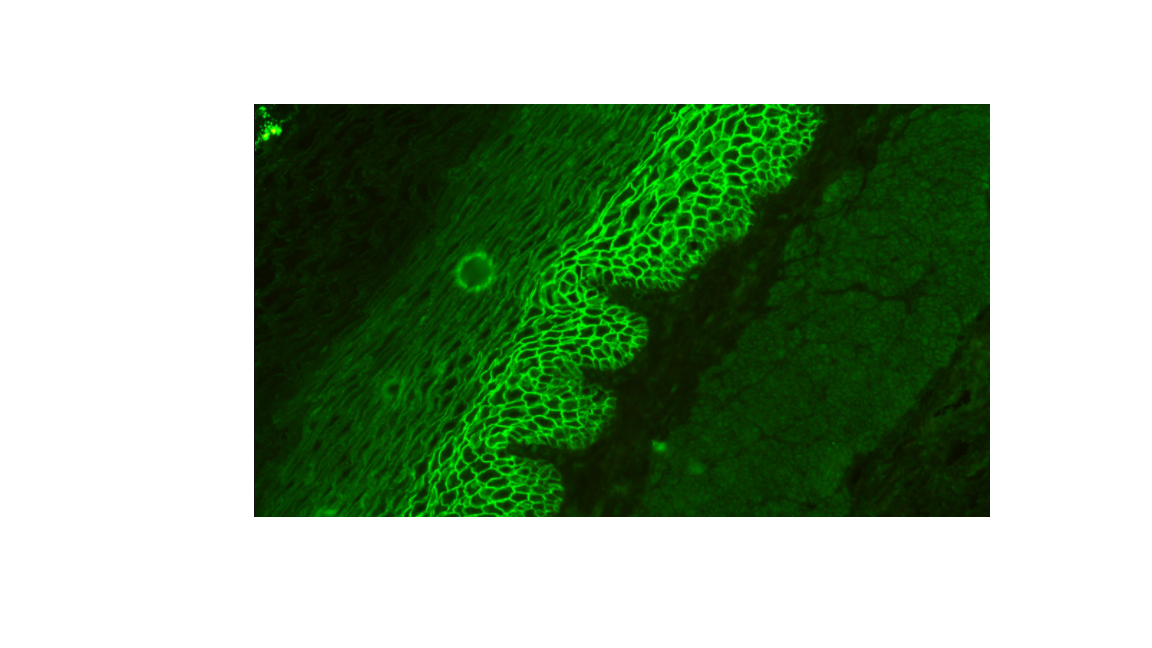

Microscopía Inmunofluorescencia Indirecta

Laboratorio Clínico Hospital de Quilpué cuenta con un microscopio de inmunofluorescencia indirecta para procesar numerosas muestras con técnicas complementarias a los Test de Screening Elisa y permite resultados confirmatorios con patrones específicos semi cuantitativos.